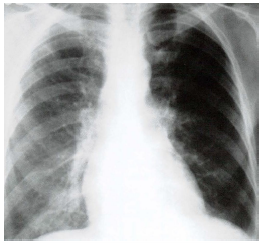

Assinale a alternativa que apresenta o sinal observado no raio x:

Médico - Radiologia